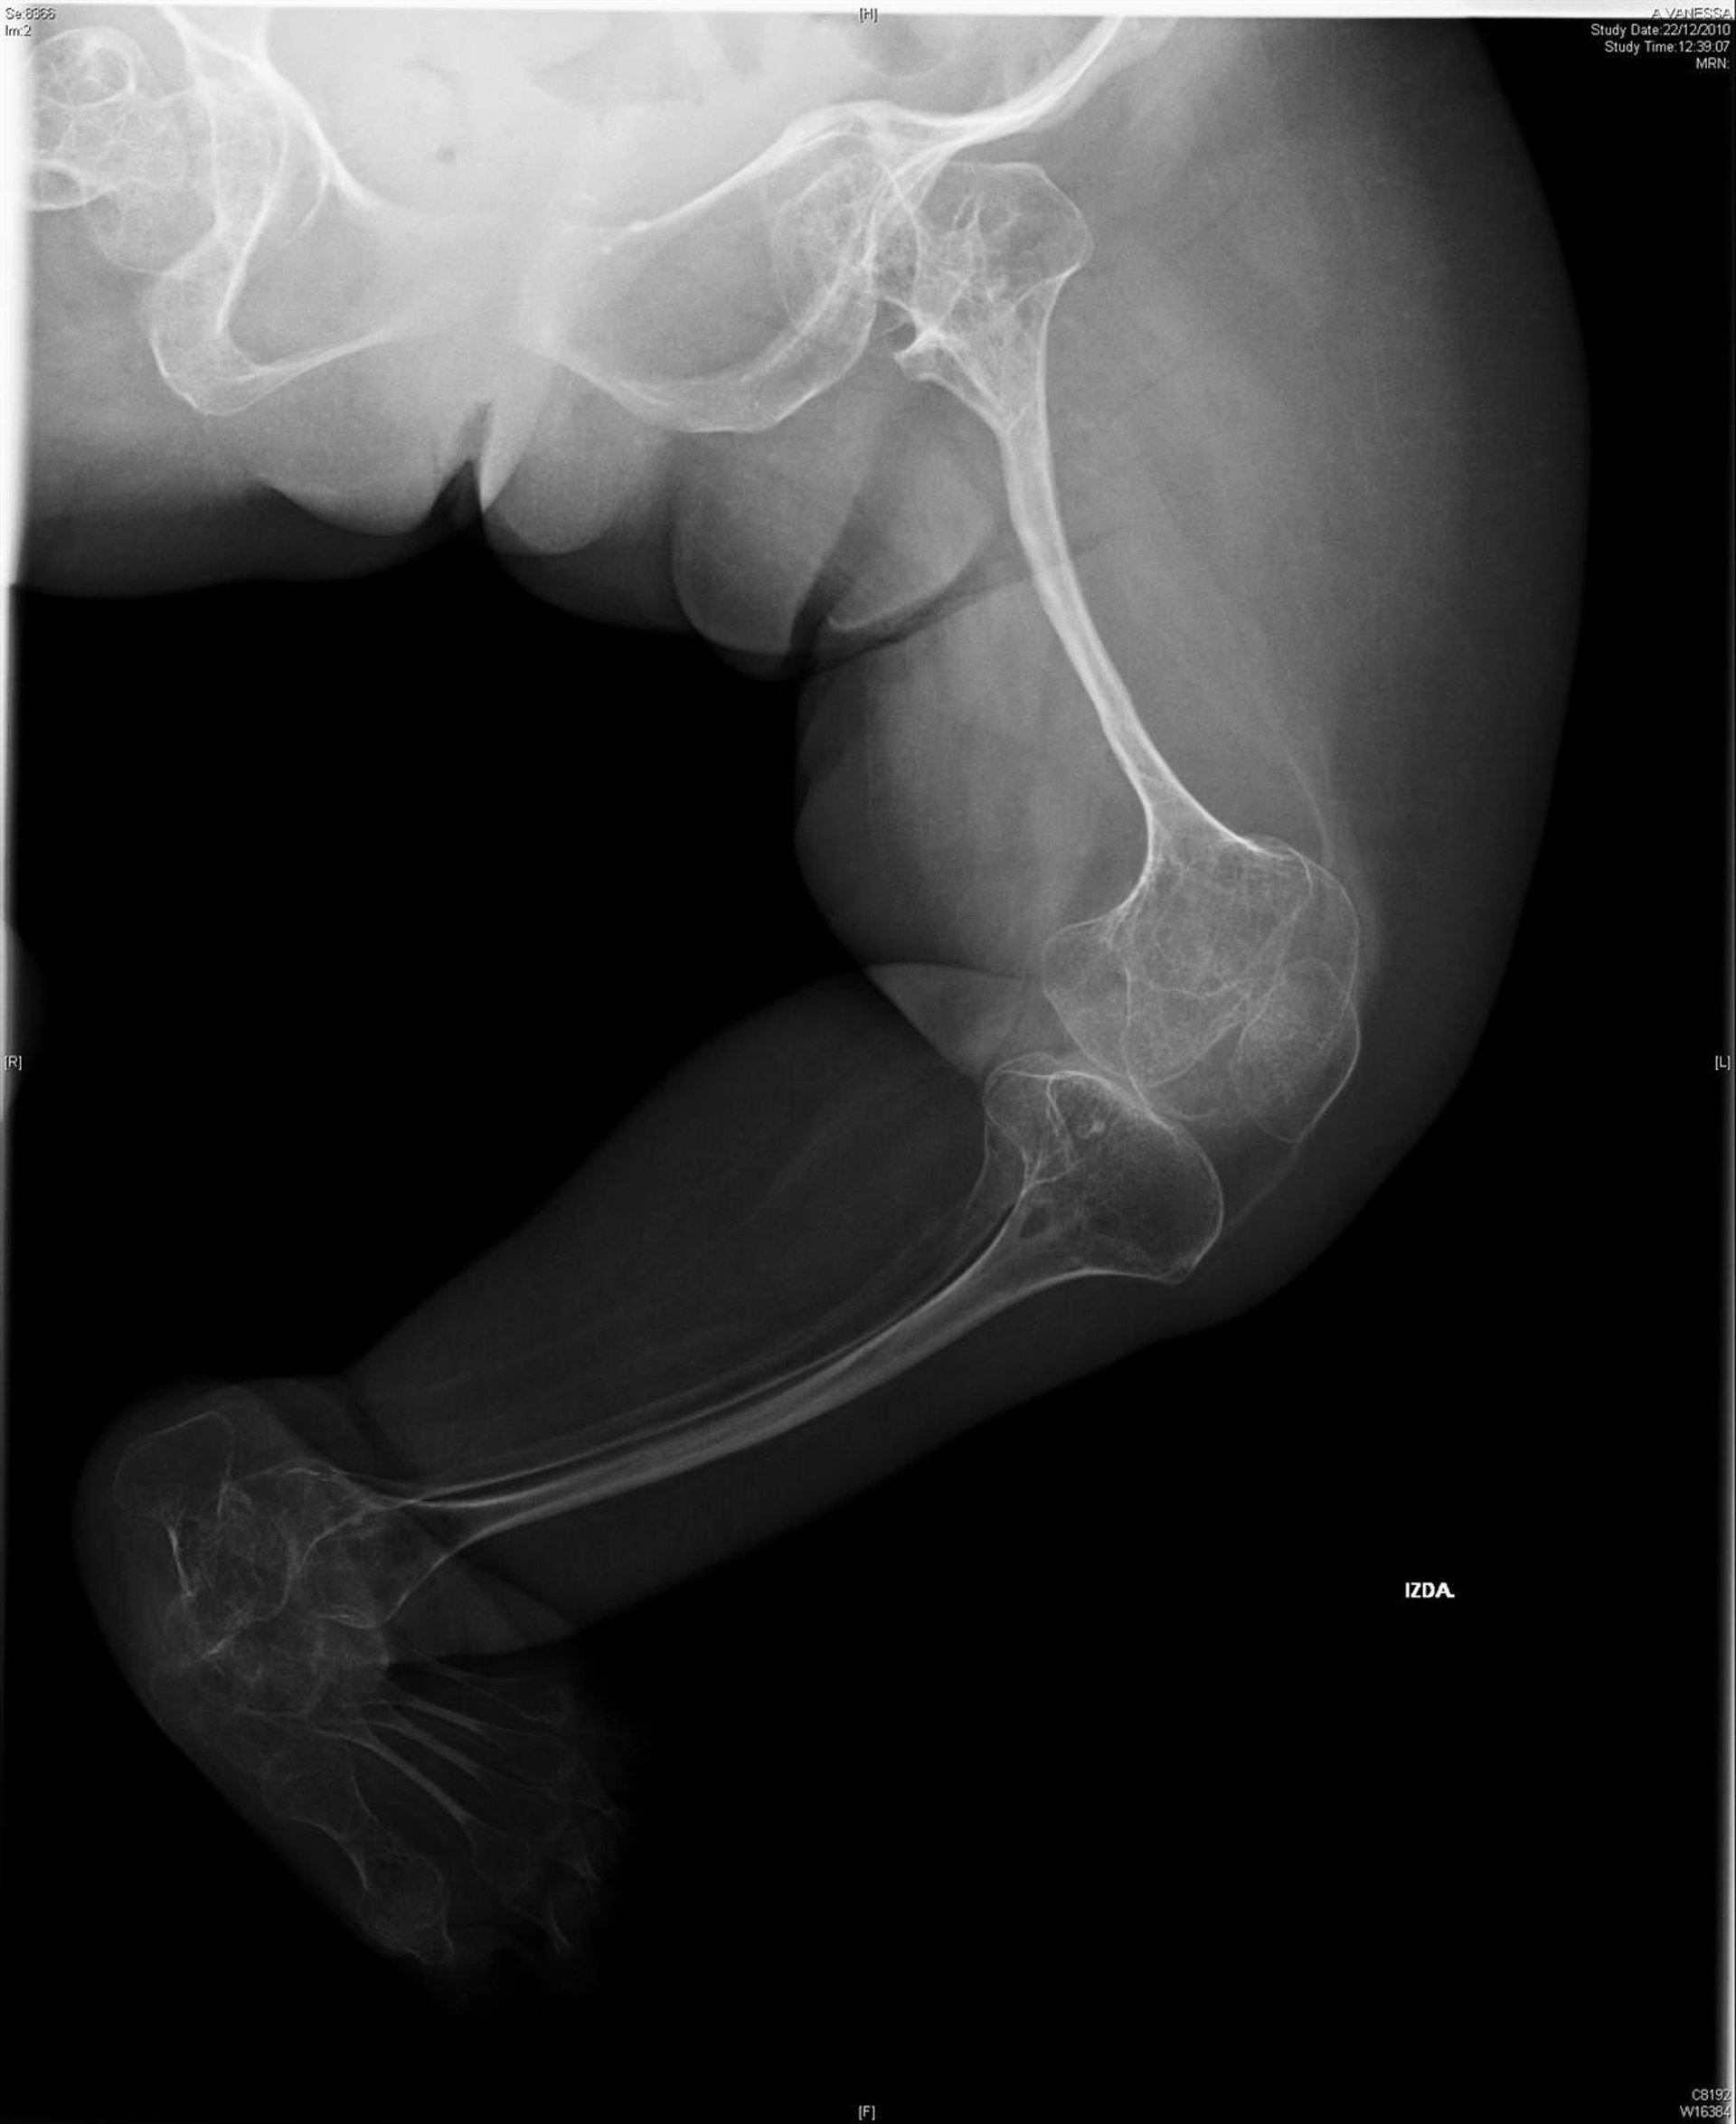

Los resultados, que aparecen publicados en la revista 'Journal of Advanced Research', se ha centrado en la osteogénesis imperfecta de tipo III, uno de los más severos y que, además, está asociado a una progresiva deformidad de la caja torácica. Asimismo, tipos adicionales han sido descritos en los últimos años al ir aumentando el conocimiento genético de la enfermedad.

La osteogénesis imperfecta fue clasificada originalmente en cuatro tipos clínicos (tipo I, II, III y IV), con una esperanza de vida diferente. Deformidades del tórax Gracias al empleo de la morfometría geométrica 3D, el grupo de investigadores ha medido la morfología de la caja torácica de pacientes con esta enfermedad y ha encontrado relaciones significativas entre la forma de las costillas y el volumen total de aire que expulsaban tras una inspiración máxima (FVC) y durante el primer segundo de una espiración forzada (FEV1).

El estudio ha revelado que las deformidades de las costillas que presentaban los pacientes estaban relacionadas con valores más bajos de ambos parámetros, es decir, FVC y FEV1. La investigación demostró que las personas afectadas con las costillas alineadas más horizontalmente, con mayor asimetría en la caja torácica, con una columna toracolumbar corta y una curvatura muy marcada en la transición toraco-lumbar, presentaban peor función respiratoria.

Estos datos confirman la hipótesis de que existe una relación directa entre las modificaciones estructurales progresivas de la caja torácica y el patrón de variaciones de volumen durante la respiración en pacientes con osteogénesis imperfecta grave.